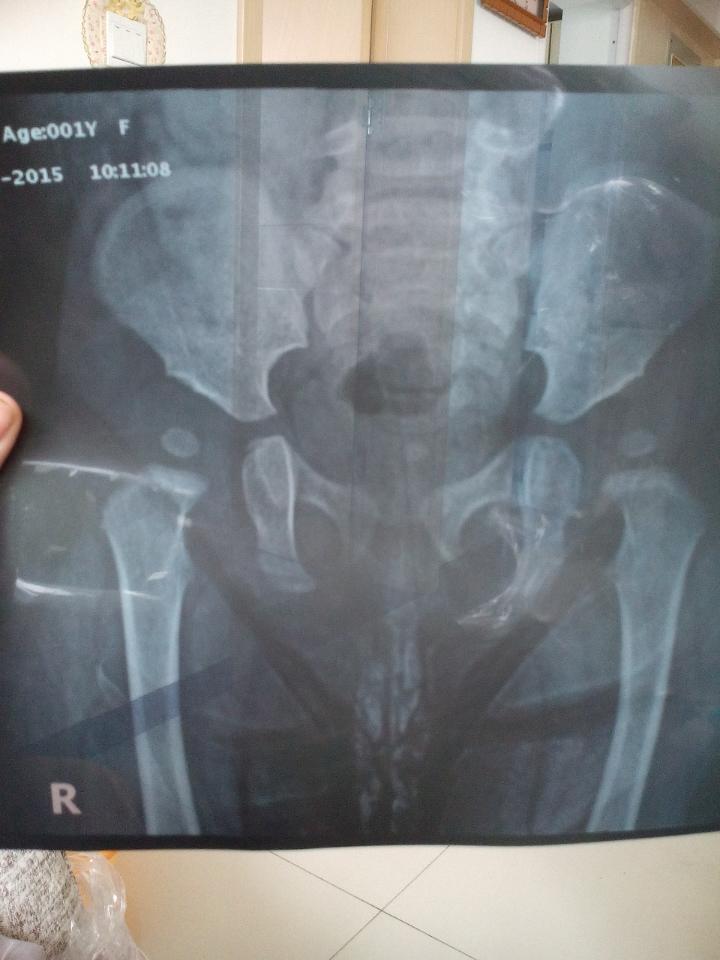

双侧髋臼发育较浅平双侧髋臼角变大 有知道这个毛病的大夫给说一下怎么看 真诚感谢 双侧髋臼发育较浅平双侧髋臼角变大。有知道这个毛病的大夫给说一下怎么看。真诚感谢 点击展开 冰冷的心_CRQt 2015-11-12 14:56 为您推荐: 其他回答 不懂,,,, ^O^魔妈^O^ 2015-11-12 16:25 问问医院怎么说 青春已去回归现实 2015-11-12 16:07 咨询一下医生 爱紫轩宝贝 2015-11-12 15:09 相关问题 双侧髋臼较浅平,髋臼上缘关节面 12个月婴儿,髋关节发育不良,经治疗初期髋臼角缩小很快,现在又突然增大 婴儿髋臼发育不良